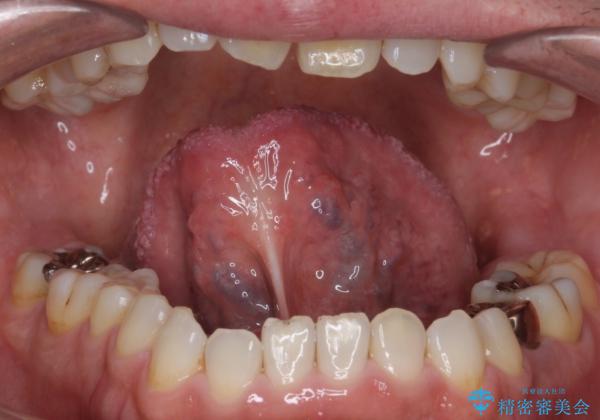

滑舌の悪さを 舌小帯形成術 で改善

局所麻酔下にて施術しました。

術後1週間で抜糸、約2週間で完全に治癒していきました。

切除後は特にラ行が言いやすくなったそうで大変喜んでいただけました。